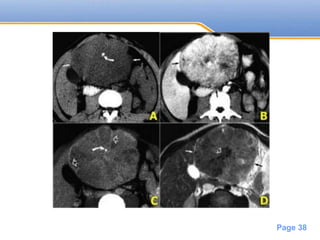

• #39 Fibrolamellar HCC On the left CT- and MR-images of a left-lobe fibrolamellar HCC in a 19-year-old man. A. Non-enhanced transverse CT scan shows calcification (curved arrow) within the hypoattenuating tumor (straight arrows). B. Hepatic arterial contrast-enhanced transverse CT scan shows heterogeneous hypervascularity within the tumor (arrows). C. Ten-minute delayed transverse CT scan demonstrates subtle areas of hyperattenuation that represent fibrous tissue within the central scar, radiating septa, and capsule (open arrows). Curved arrow = calcification. D. Transverse T2-weighted MR image (5,000/105) also demonstrates the central scar and septa (open arrow). The tumor itself (straight arrows) is nearly isointense to liver